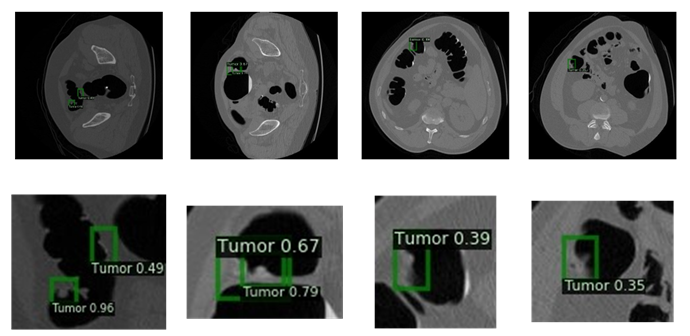

基于广域语义图像外推做数据扩充的结直肠息肉检测方案

作品简介:结直肠息肉检测的难点在于它需要依赖带有标注的大型数据集的监督训练。基本的图像翻转、旋转、平移等操作实现的图像扩充很难大幅度提升检测系统的效能;另外,由于图片上的息肉都是由医学专家利用专业知识、花费大量时间标注而成,具备真实性及权威性,而使用生成对抗网络进行息肉的生成就会面临真实性无法判断的问题。因此本作品使用语义图像外推的思想,提出了一种新颖的应用于医学图像的数据扩充方案。它首先对现有数据集的息肉部分进行裁剪,保证息肉的真实性;然后采用广域语义外推技术进行息肉外围图像的生成,从而实现对数据集的进一步扩充。同其他方法相比,该方法生成的图像更具有说服力, 实验效果验证了该数据集检测结果的优越性。而后,我们构建了Yolo-V3网络实现了结肠息肉的检测,实验结果显示,经过数据扩充后的模型指标取得了明显的提高。